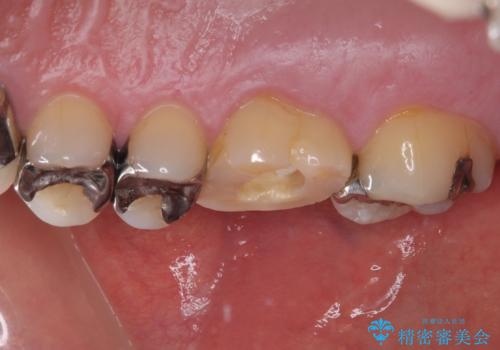

治療途中の奥歯 オールセラミッククラウンでのむし歯治療

初回の根管治療時に仮歯を装着しましたが、仮歯を介して食事などを行っても痛みは感じなくなっており、その後は速やかに補綴治療を行いました。